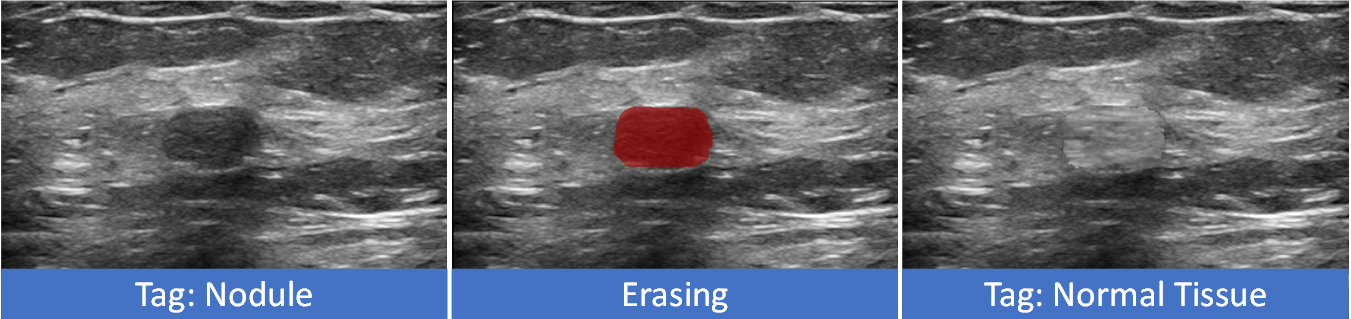

Refer to caption

Fig. 2: Motivations of flip learning: erasing the nodule from the original image (red region) and inpaint the erased region can flip its tag.

In our prior MICCAI research, we introduced a MARL-based WSS method called Flip Learning to enhance precise segmentation using basic box annotations [34]. In our proposed framework, the agents erase the nodule within the box, and the erased region is filled based on the pre-generated eraser source. Through erasing, the classification score of nodule will drop progressively, making the image tag flip from “nodule” to “normal tissue”. The erased region will be considered as the final segmentation prediction. The motivation for our proposed work can be summarized in mainly two aspects:

Why erasing and tag-flipping for segmentation? Let’s say we want to change the tag of an image, for instance, switching from foreground (nodule) to background (normal tissue). See Figure 2, one of the simplest approaches is to remove the object (i.e., nodule) from the image and then fill the removed area using methods similar to inpainting [20]. If the erasing is done accurately, it is possible to extract the erased region and convert it into a segmentation mask.